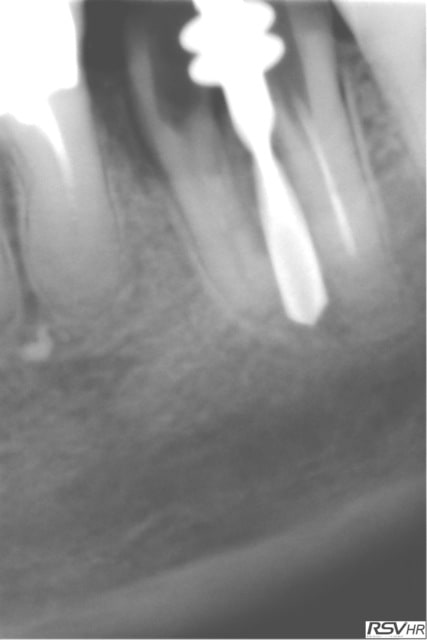

même patiente pour 46

extraction le 31.03.2012 avec le même jour pose implant legacy

cette fois long10mm diamètre 4.7mm

toujours la technique forage entre racines extraction reforage pose implant

le 13.09.2012 couronne céramométallique sur fM